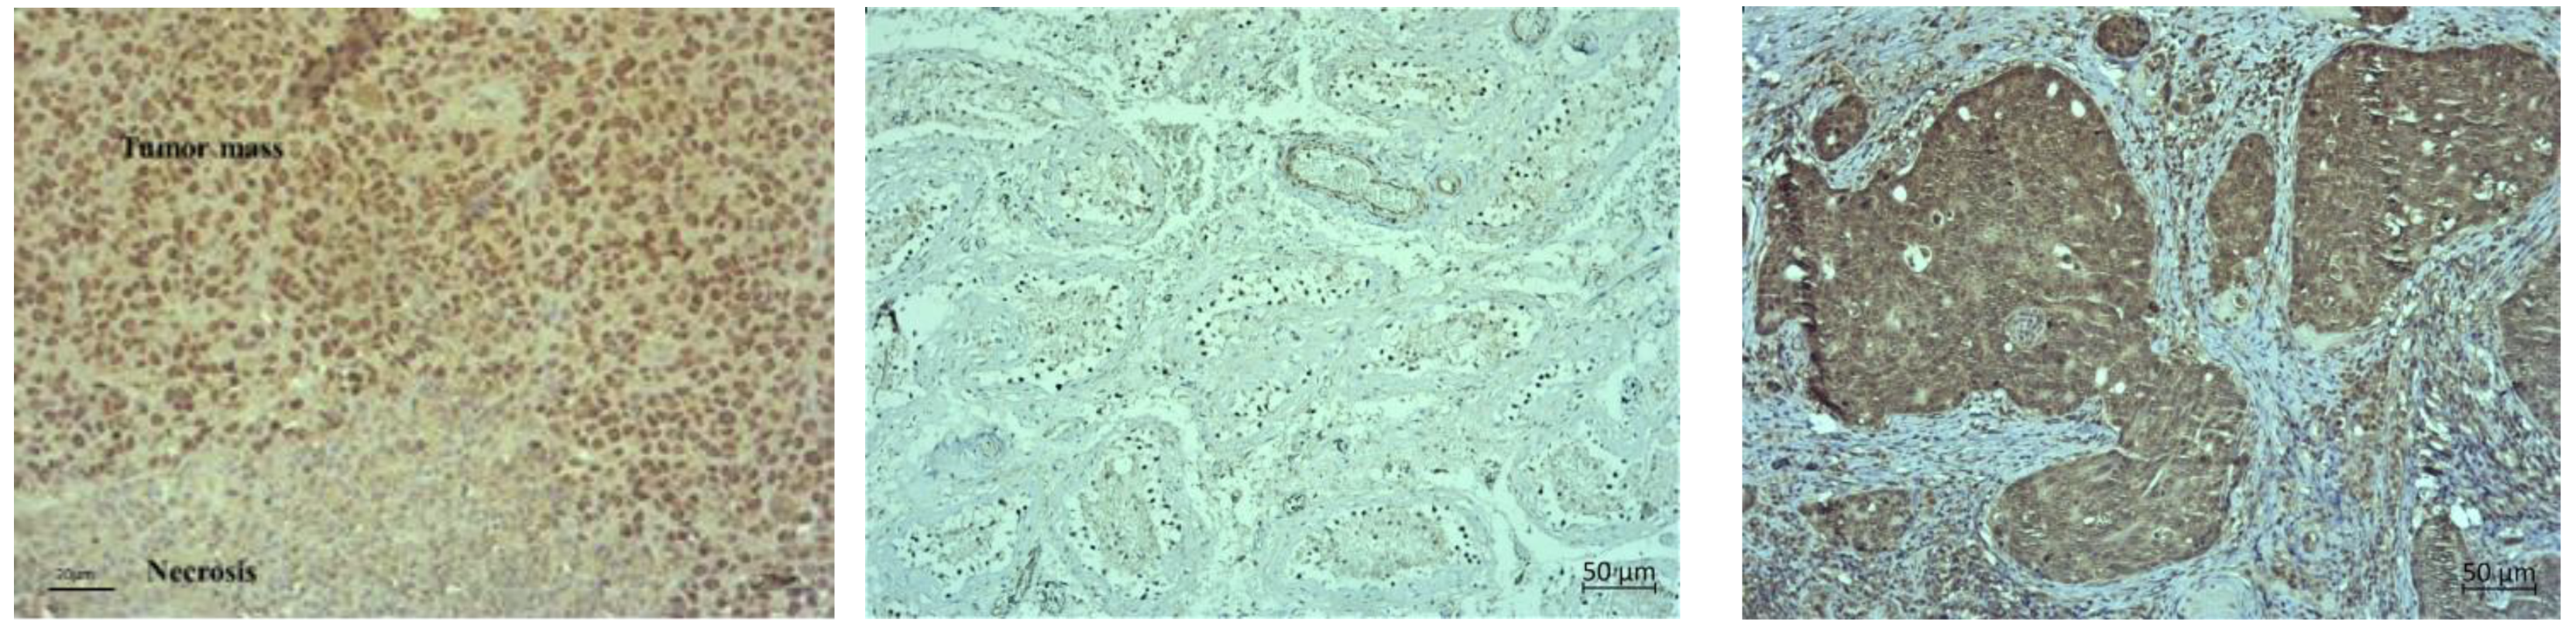

2.4. Combination of Resveratrol, Cisplatin, and Hyperthermia Induces Histological and Immunohistochemical Changes in Tumour Tissue of Balb/c Mice Bearing the Solid Form of EAT

The pathological examination of the paraffin-embedded solid EAT samples showed visible central necrosis in all specimens, the degree of which cannot be assessed (Figure 10, first rows on Figure 11 and Figure 12). In all samples, the tumour cells were located at the periphery of the tumour mass and showed a very high degree of proliferation (more than 90%). Therefore, in Figure 10 we showed one representative example of nuclear positivity for the proliferating cell nuclear antigen (PCNA). However, it is clearly visible that the treated samples showed different patterns of necrosis (Figure 11 and Figure 12). For the single-agent treated samples, we observed the most extensive necrosis following treatment with Cis and then Res.

Hypoxia inducible factors 1 and 2 (HIF) are important transcriptional regulators of angiogenesis and energy metabolism in tumours and an important target for cancer therapy [20]. Accumulating evidence indicates that inhibitors of histone deacetylases repress the function of HIF in tumour cells through yet unclear pathways. Based on the above, we investigated HIF activity, as well as the key factors of angiogenesis (VEGF, MMP2, and MMP9) and the number of blood vessels.

After immunohistochemical staining, we observed weak cytoplasmic staining for HIF-1α in control and single-agent treated samples (Figure 11). Although the solid EAT tumour (Control) showed focal cytoplasmic staining, we did not observe any nuclear staining indicative of transcriptional activation of hypoxia-activated signalling pathways. Testicular cancer was used as a positive control for hypoxia-inducible factor 1 (HIF-1α), with clear nuclear positivity (Figure 10).

Immunohistochemical staining for inducible nitric oxide synthase (iNOS) showed weak to moderate cytoplasmic staining for iNOS in control and single-agent treated samples. The strongest expression was observed in samples treated with Cis. Breast cancer was used as a positive control for iNOS with strong cytoplasmic staining (Figure 10).

After immunohistochemical staining, we observed moderate cytoplasmic staining for HIF-1α in all samples treated with combined agents (Figure 12). The staining was more intense than the Control or single-agent treated samples. However, moderate cytoplasmic staining with sporadic stained nuclei was observed in Res + Cis + HT and Cis + HT groups while some sporadic stained nuclei were observed only in Res + Cis + HT, compared to staining in all other treatment groups.

The immunohistochemical staining for iNOS also showed moderate cytoplasmic staining in all samples treated with combined agents. The strongest expression of iNOS was observed in samples treated with Cis + HT and Res + Cis + HT.